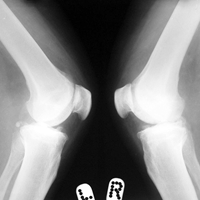

Arthroscopy Surgeon in Ahmedabad

Pre-Op AP

Pre-Op Lateral